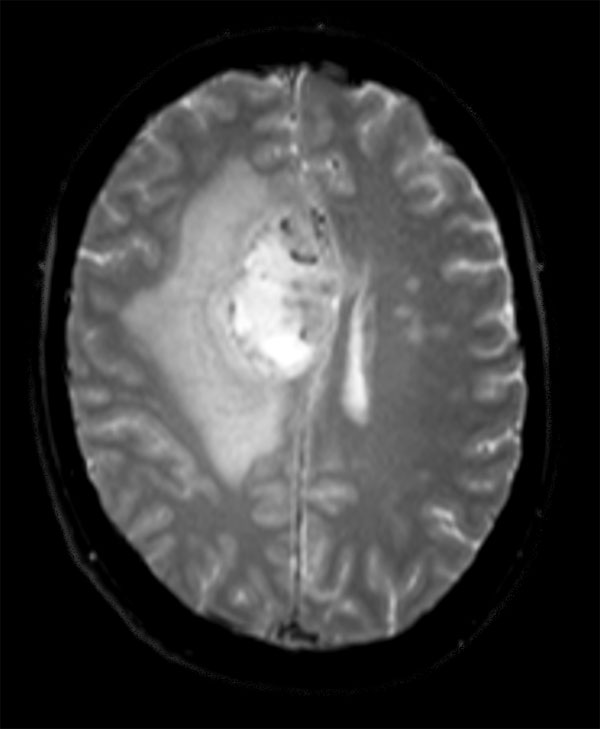

Advanced Neuro imaging - pCASL

Clinique Saint Joseph Imagerie Medicale, Liege, Belgium